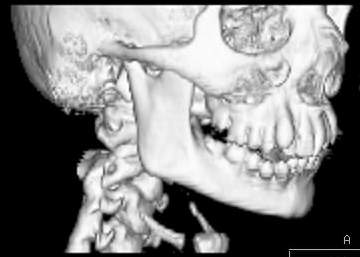

Пациент В., 13 лет. Диагноз: Костный анкилоз левого височно-нижнечелюстного сустава (ВНЧС), левосторонняя микрогения. Болеет с 2-х летнего возраста. Возможная причина развития анкилоза – воспалительный процесс (в первые 1,5 года жизни часто болел простудными заболеваниями, травму родители отрицают). В 3 и 5 лет проводилась редрессация – безуспешно.Прилагаются: ортопантомограмма, кадры СКТ с 3Д реконструкцией. Вопросы: определение тактики лечения – вид и сроки реконструктивно-пластической операции (этапов операции), а именно – неоартропластики и устранения микрогении, медикаментозная терапия в до- и послеоперационный период, ортодонтическое лечение.

Возможно проведение традиционной остеотомии с введением дермо-жирового трансплантата в линию остеотомии. Сроки ортодонтического лечения необходимо обсуждать совместно с ортодонтом и планировать начало лечения до и после оперативного вмешательства. Не исключено применение в дальнейшем остеотомии убоальвеолярных отростков с целью коррекции прикуса.

Мнение, высказанное специалистами из Питера, совпадает с нашим мнением и на следующей неделе мы планируем проведение указанного оперативного вмешательства (1-ый этап лечения). Если кому-то интересно, напишите мне на личный e-mail, представлю дальнейшие материалы по данному случаю.